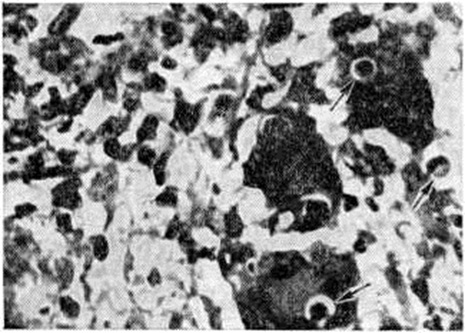

Морфологически изменения в лёгких при кокцидиоидозе разнообразны: очаги уплотнения лёгочной ткани, обширные студенистые очаги или очаги нагноения, некротический язвенный бронхит, гранулематозные поражения без некроза и очаги обызвествления с некрозом в центре. Реже встречающийся вторичный кокцидиоидоз лёгких имеет сходство с туберкулёзом. При этом наблюдаются казеозная пневмония, абсцессы, в которых обнаруживают сферулы грибка (рисунок 3). Клинические, проявления болезни могут ограничиваться признаками острого респираторного заболевания. Спустя несколько недель наступает выздоровление. У 4—5% инфицированных лиц кокцидиоидоз с поражением лёгких протекает в тяжёлой форме, сопровождается высокой температурой, одышкой, кашлем с гнойной мокротой, иногда кровохарканьем. Наблюдаются резкие колебания температуры в течение суток, сопровождающиеся ознобами и потами. Больные жалуются на головную боль, боль в мышцах, пояснично-крестцовой области. В последующем развиваются анорексия, астения, снижается вес (масса) тела больных. Над лёгкими выслушиваются сухие и влажные хрипы, иногда — шум трения плевры. В течении болезни отмечаются длительные периоды ремиссии. Иногда наблюдается диссеминация возбудителя инфекции и развитие грибкового сепсиса с образованием множественных абсцедирующих инфильтратов в различных органах и тканях.

Рис. 3.

Микропрепарат лёгкого при кокцидиоидозе: в центре инфильтрата зрелая сферула Coccidioides immitis, заполненная эндоспорами; окраска гематоксилин-эозином; ×600.